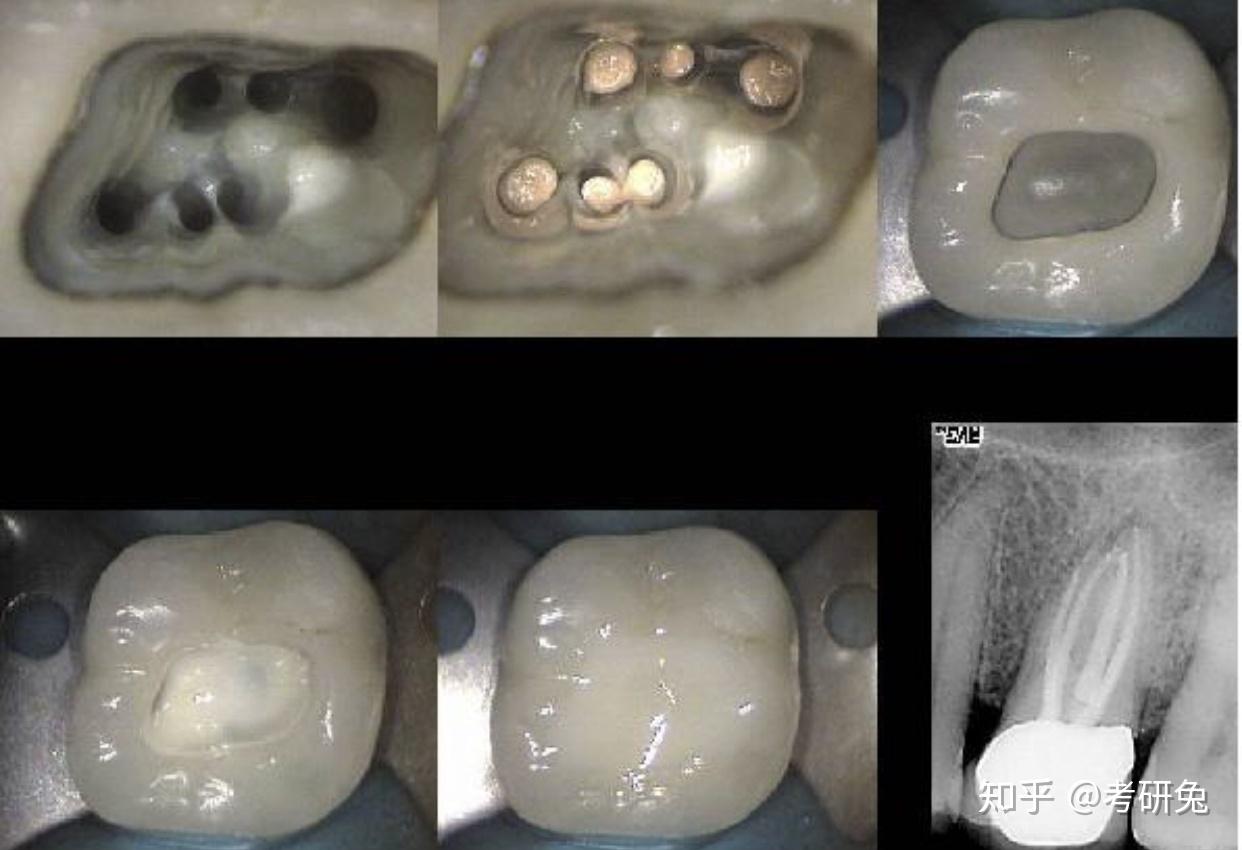

夹层修复技术